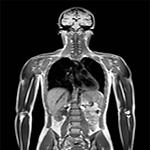

- МРТ всего тела